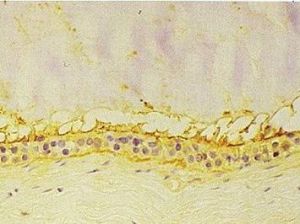

(1)表皮囊腫:是一種真皮內含有角質囊腫。系因外傷將表皮植入皮下而成。其囊腫壁為上皮結構,但基底細胞層為囊壁外層。角質層為囊壁內層並充滿角質物於腔內。

(2)皮樣囊腫:常為先天性病變,由於胚胎期上皮殘留而發生,屬錯構瘤,是由於偏離原位的皮膚細胞原所構成。除囊壁表皮細胞外,尚含汗腺、毛囊及皮脂腺等。腔內含有脫落的上皮細胞、皮脂等粥樣物及有毛髮。

(3)粉瘤由皮脂腺囊管口閉塞或狹窄所引起皮脂瘀積形成。腔壁為上皮細胞構成,無角化象,囊外為纖維結締組織。其內充滿皮脂物逐漸分解為半流質狀物質,含有大量膽固醇結晶。